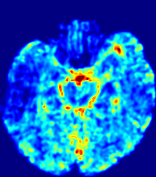

Slice #1Slice #2Slice #3Slice #4Slice #5Slice #6Dgtsuperscript𝐷gtD^{\text{gt}}Refer to captionRefer to captionRefer to captionRefer to captionRefer to captionRefer to caption(a)Refer to captionRefer to captionRefer to captionRefer to captionRefer to captionRefer to caption(b)Refer to captionRefer to captionRefer to captionRefer to captionRefer to captionRefer to caption(c)Refer to captionRefer to captionRefer to captionRefer to captionRefer to captionRefer to caption(d)Refer to captionRefer to captionRefer to captionRefer to captionRefer to captionRefer to caption(e)Refer to captionRefer to captionRefer to captionRefer to captionRefer to captionRefer to caption(f)Refer to captionRefer to captionRefer to captionRefer to captionRefer to captionRefer to captionRefer to caption000.060.060.060.120.120.120.180.180.180.240.240.240.300.300.30(mm2/s)𝑚superscript𝑚2𝑠(mm^{2}/s)

Figure 13: PIANO effectiveness and robustness testing: diffusion imaging via diffusion. Top row shows Dgtsuperscript𝐷gtD^{\text{gt}} used for simulating the ground truth pure diffusion. (a)-(f) refer to the results for D𝐷D estimated from the ground truth pure diffusion image time-series where Rician noise at levels 0%, 2%, 4%, 6%, 8%, 10% was added respectively.

Similarly, starting from the same initial condition C0superscript𝐶0C^{0} as in the ‘Advection Imaging’ experiment for each patient, we simulate concentration time-series {Cti(Ω)|i=0, 1,, 40}conditional-setsuperscript𝐶subscript𝑡𝑖Ω𝑖0140\{C^{t_{i}}\in\mathbb{R}(\Omega)|i=0,\,1,\,\ldots,\,40\} via a diffusion PDE, where we define the ground truth diffusivity D:=Dgtassign𝐷superscript𝐷gtD:=D^{\text{gt}} via the ADC map of the ISLES 2017 training set (ADC values are scaled by 0.000010.000010.00001 to ensure numerical stability):

Note this is likely not a spatially representative ground-truth for perfusion imaging, as it measures different effects from diffusion imaging. However, we still use it as a quasi-realistic pattern of diffusivity in the brain. We also added 2%, 4%, 6%, 8%, 10% levels of Rician noise to obtain simulations of ‘Diffusion Imaging’. The estimated Destsuperscript𝐷estD^{\text{est}} given concentrations of all noise levels for one patient are shown in Fig. 13, PIANO estimation results for all patients are summarized in Fig. 11 (b). Again, PIANO demonstrates its capability to recover the underlying diffusion field. In Fig. 13, when the noise level is increasing, some noisy patterns indeed appear in the associated Destsuperscript𝐷estD^{\text{est}}. Note that the ground truth diffusivity applied in this simulation experiment is about ten times larger than the diffusivity estimated in reality (Fig. 3, Fig. 4).